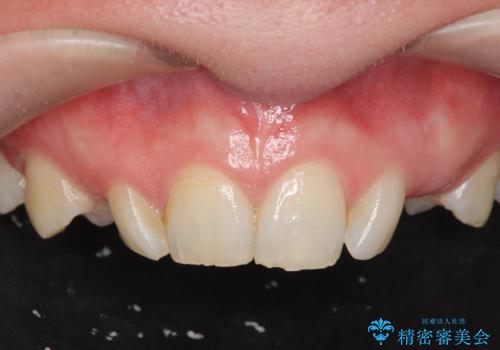

骨造成を伴う 前歯部インプラント治療

- 欠損している前歯のインプラント治療を希望され来院されました。

適切なインプラント埋入を行い、不足している骨量を補うため骨の造成を併用したインプラント治療を計画します。

前歯のインプラント治療は骨量・歯肉の厚み・インプラントの方向をしっかりと計画することで、審美的で長持ちを期待できるような仕上がりとなります。